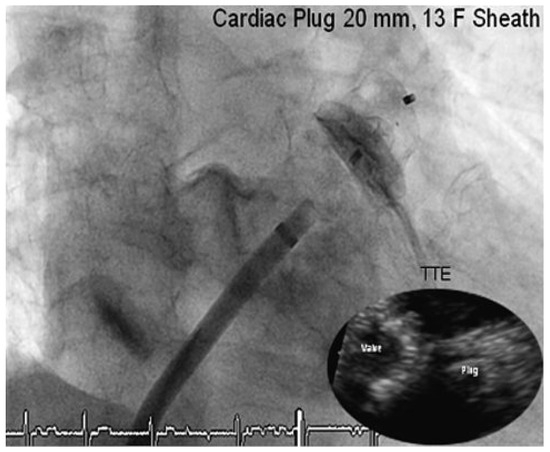

Case Report

Comprehensive “One Stop-Shop” Percutaneous Cardiac Intervention

by Thomas Pilgrim, Peter Wenaweser, Stephan Windecker and Bernhard Meier

Cardiovasc. Med. 2010, 13(5), 171; https://doi.org/10.4414/cvm.2010.01497 - 26 May 2010

Abstract

A 78-year-old male retired mathematician with severe aortic stenosis, persistant atrial fibrillation, reluctance to accept oral anticoagulation, and with suspected coronary artery disease was referred for further management [...] Full article

Show Figures

Figure 1